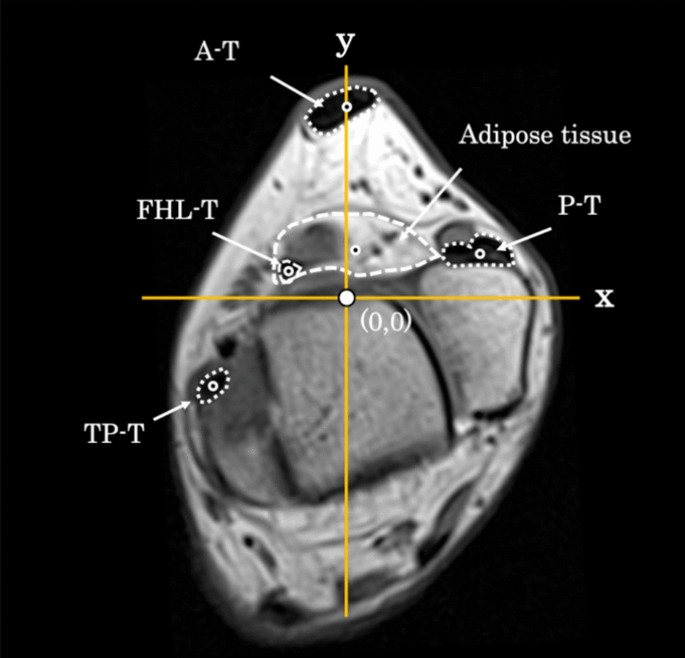

Examining the positional relationship between the FHL tendon and surrounding adipose tissue

The location of adipose tissue around the FHL tendon relative to the tendon around the ankle joint was examined. Based on the slice level of the trochlea of the talus, a straight line passing through the center of the talus and center of the Achilles tendon was defined as the y-axis, and the line perpendicular to the y-axis passing through the maximum bulge of the lateral malleolus was defined as the x-axis, with an intersection point at the origin (0, 0) (Fig. 1). Positive values were defined as lateral or posterior, whereas negative values were defined as medial or anterior.

Coordinate axis settings. X-axis: Straight line to the Y-axis through the maximum bulge of the lateral malleolus. Y-axis: Straight line through the center of the talus and center of the Achilles tendon. Red circle: each center point; yellow circle: origin. FHL-T, flexor hallucis longus tendon; A-T, Achilles tendon; P-T, peroneal tendon; TP-T, tibialis posterior tendon; T, talus, MM, medial malleolus; LM, lateral malleolus; Pos, posterior; Ant, anterior; Lat, lateral, Med: medial.

Thereafter, we measured the coordinate centers of the FHL tendon and surrounding reference adipose tissue, the Achilles tendon, peroneal tendon, and tibialis posterior tendon to confirm their positional relationships. The coordinate center was measured using ImageJ software (v.1.53, National Institutes of Health, USA, https://imagej.net/ij/index.html).

The coordinate centers (x, y) of the FHL tendon, adipose tissue, Achilles tendon, peroneal tendon, and tibialis posterior tendon are presented in Table 3. Additionally, the coordinate center of the adipose tissue surrounding the FHL tendon was located at a level (y value) similar to that of the peroneus tendon (Fig. 9).